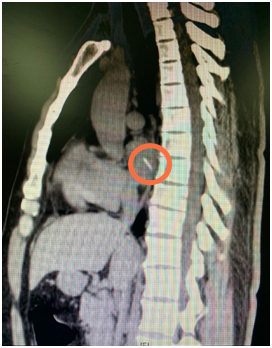

胸部CT片  画圈处为鱼刺

福建省立医院心外科主任医师谢琦分析,这根刺刺穿食管后,随着阿福的不断进食吞咽,又刺进了邻近的左心房并被完全推了进去。来自唾液和鱼刺上的细菌从被扎的破口向外侵袭并不断繁殖,导致阿福出现血液感染并诱发高烧。由于人体的食管和心肌几乎没有痛觉,耽误了阿福找到病因。